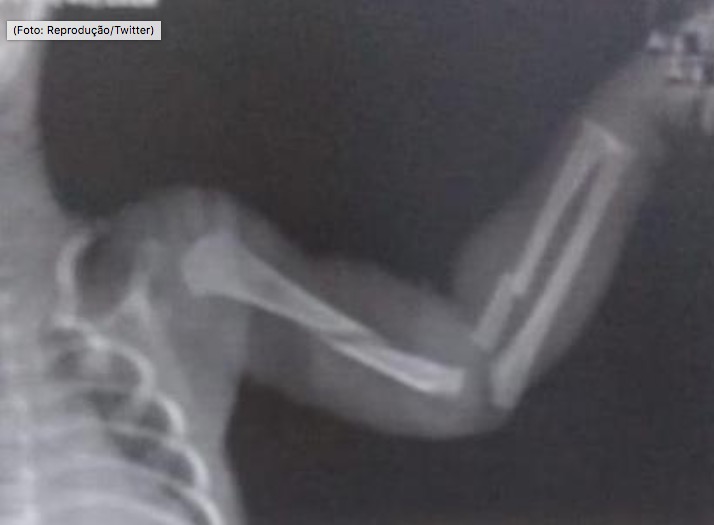

A mãe de um bebê de apenas dois meses foi presa na manhã desta sexta-feira (3) após a criança dar entrada no hospital com múltiplas fraturas. Foi a equipe médica do Hospital Estadual Adão Pereira Nunes, em Duque de Caxias, estado do Rio de Janeiro, que chamou a polícia após ver o estado do menino.

Segundo a Rede TV, a Polícia Civil do Rio informou que, no próprio hospital, os agentes de segurança ouviram a mulher que negava o crime, mas depois acabou confessando. A polícia acredita que as fraturas não foram causadas por um acidente, mas por agressões violentas e sucessivas.

A mãe ainda confessou para a polícia que essa não foi a primeira vez que bateu no filho de dois meses. Segundo a poícia, ela foi autuada em flagrante pela prática de crime de maus tratos qualificado pela lesão corporal de natureza grave.